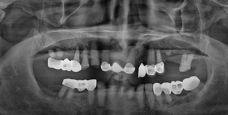

전